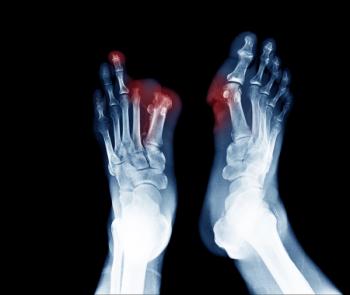

Lower limb amputations are devastating for people living with diabetes, particularly for Black Americans facing poor access to comprehensive care. A coordinated, data-driven national prevention strategy is the only way to curb this growing epidemic for all at-risk populations.